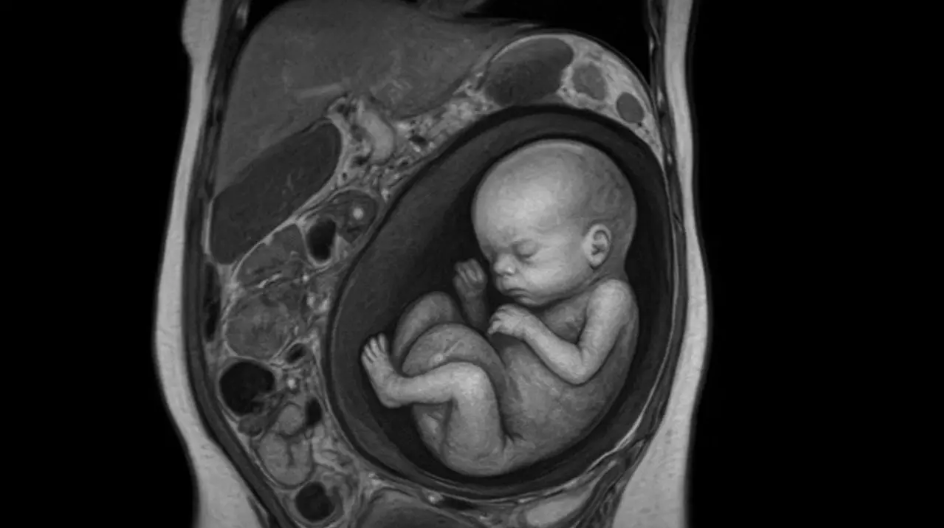

उत्तर प्रदेशातील बुलंदशहर जिल्ह्यातील एका दुर्मिळ गरोदरपणाच्या घटनेने डॉक्टरांना धक्का बसला आहे. या भागातील ३० वर्षीय महिलेला सतत पोटदुखीचा त्रास होत होता आणि तिने अखेर वैद्यकीय मदत घेण्याचा निर्णय घेतला. यानंतर तिचा एमआरआय रिपोर्ट पाहून डॉक्टरही थक्क झाले. महिलेच्या गर्भाशयात नाहीतर यकृतात १२ आठवड्यांचा गर्भ वाढत असल्याचे समोर आले.

महिलेच्या यकृताच्या उजव्या भागामध्ये गर्भ आढळून आला, असे तपासणी करणारे रेडिओलॉजिस्ट डॉ. के. के. गुप्ता यांनी सागितले. स्कॅन दरम्यान त्यांना गर्भाच्या हृदयाचे ठोके देखील आढळले. बुलंदशहर येथील रहिवासी असलेली ही महिला गृहिणी आहे आणि आधीच दोन मुलांची आई आहे. तिचा नवरा एका खाजगी कंपनीत नोकरी करतो.

वैद्यकीय सूत्रांच्या मते, भारतात यापूर्वी कधीही असा कोणताही रुग्ण आढळलेला नाही. २२ जुलै रोजी एमआरआय करणारे डॉ. गुप्ता यांनी असामान्य निदानाची पुष्टी केली. “ही १२ आठवड्यांची गर्भधारणा होती जी गर्भाशयाऐवजी यकृतात होती,” असे ते म्हणाले.

त्यांनी पुढे सांगितले की स्कॅननंतर, त्यांनी या स्थितीचा सखोल अभ्यास केला आणि त्यांना आढळले की ही एक अत्यंत दुर्मिळ घटना आहे, आजपर्यंत जगभरात असे फक्त १८ प्रकरणे नोंदवली गेली आहेत. त्यांनी पुढे स्पष्ट केले की, अशी गर्भधारणा १४ आठवड्यांपेक्षा जास्त काळ पुढे नेता येत नाही, कारण ती आईच्या आयुष्यासाठी घातक ठरू शकते.